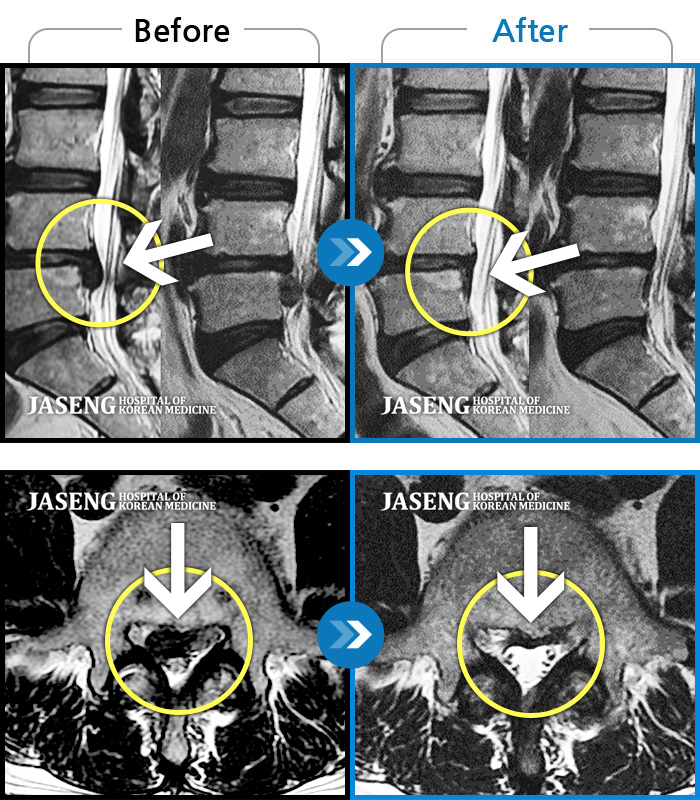

[뱸] 19.11.28~25.05.06

ȯںп Ǹ ǿ ԿǾ, ο ġ ۿ Ƿ ġḦ Ͻñ ٶϴ.